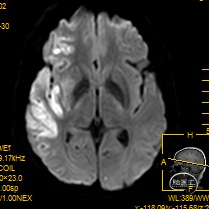

03 术前影像资料

溶栓前颅脑CT提示考虑右侧大脑中动脉致密征,支持大脑中动脉为责任病变。

溶栓后颅脑CT见右侧大脑中动脉远端致密征,右外侧裂池变窄,同并见“岛带征”,考虑右侧急性脑梗塞,必要时进一步MR检查和/或CT脑灌注成像。

术前MRA显示右侧大脑中动脉远端变窄并分支稀疏。